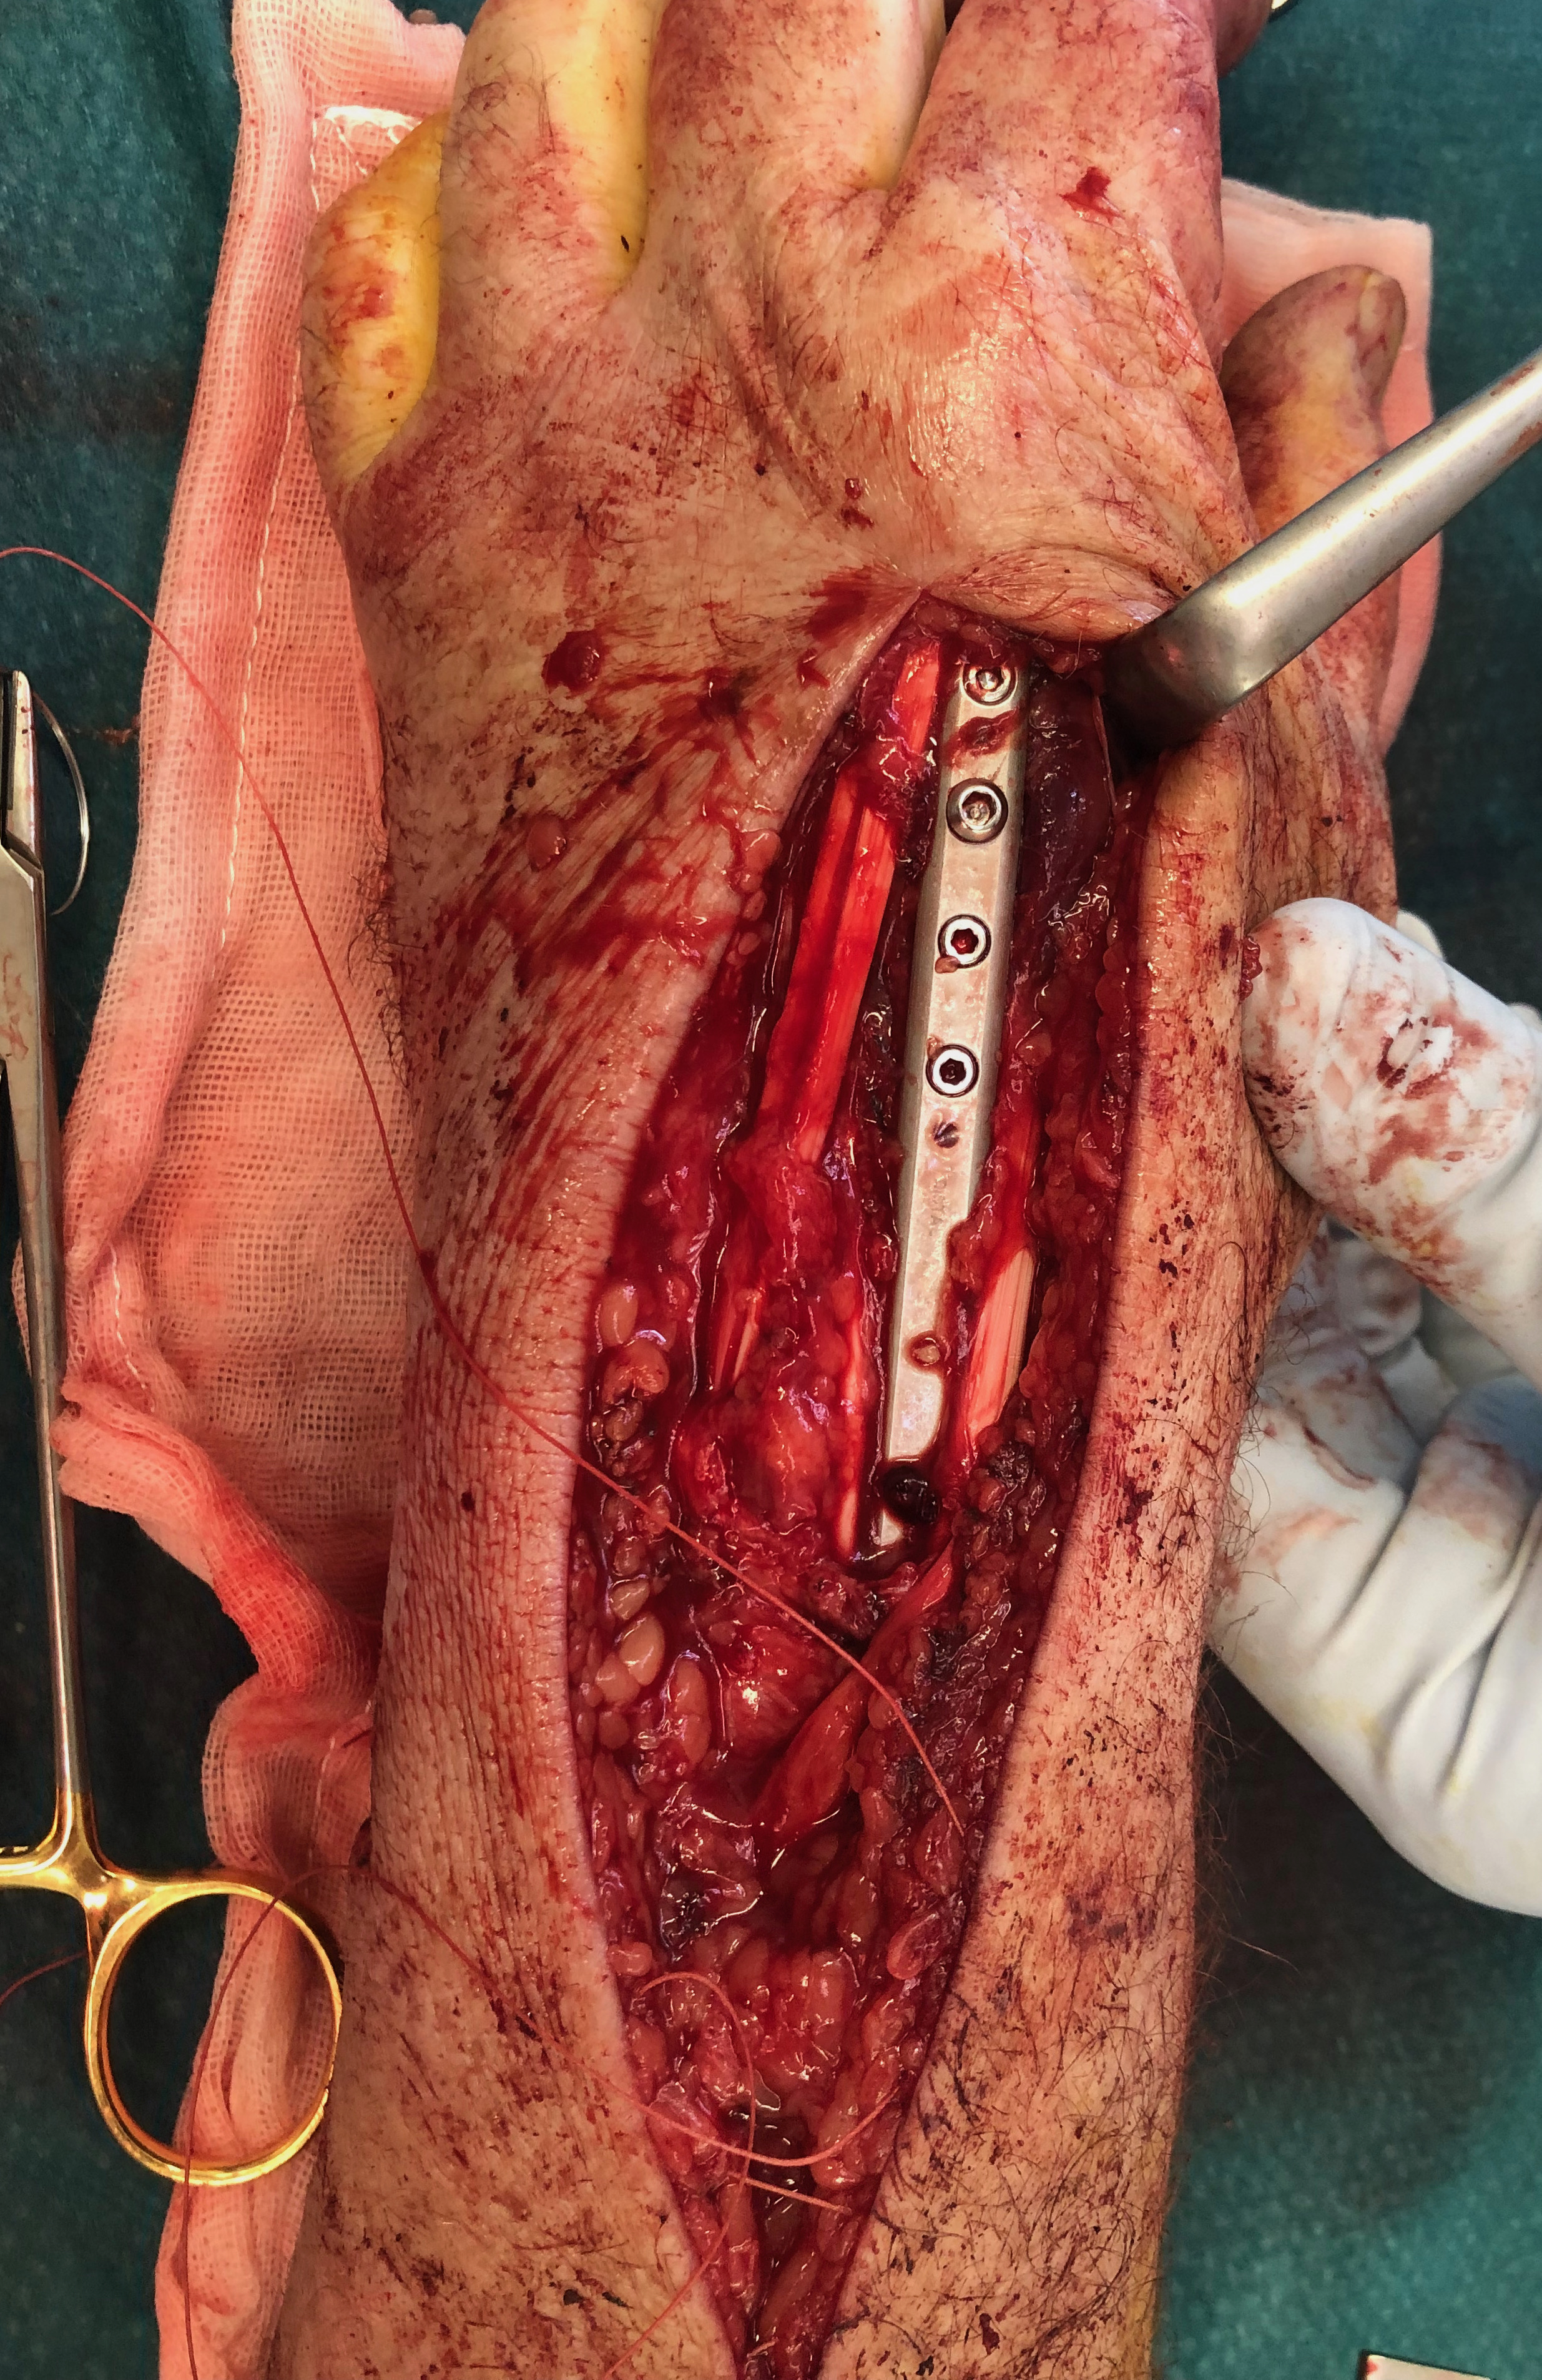

Dorsal distraction plating

Technique

Extended dorsal approach

- protect sensory radial nerve

- open 3rd extensor compartment / retract EPL radially

- mobilized 4th extensor compartment / retract EDC ulnarly

- bare area of radius proximally between EDC and ECRB / ECRL

Fixation to 2nd or 3rd metacarpal first

- 2nd metacarpal: under 2nd extensor compartment

- 3rd metacarpal: under 4th extensor compartment

- reduce / distract joint

- +/- additional radius fixation